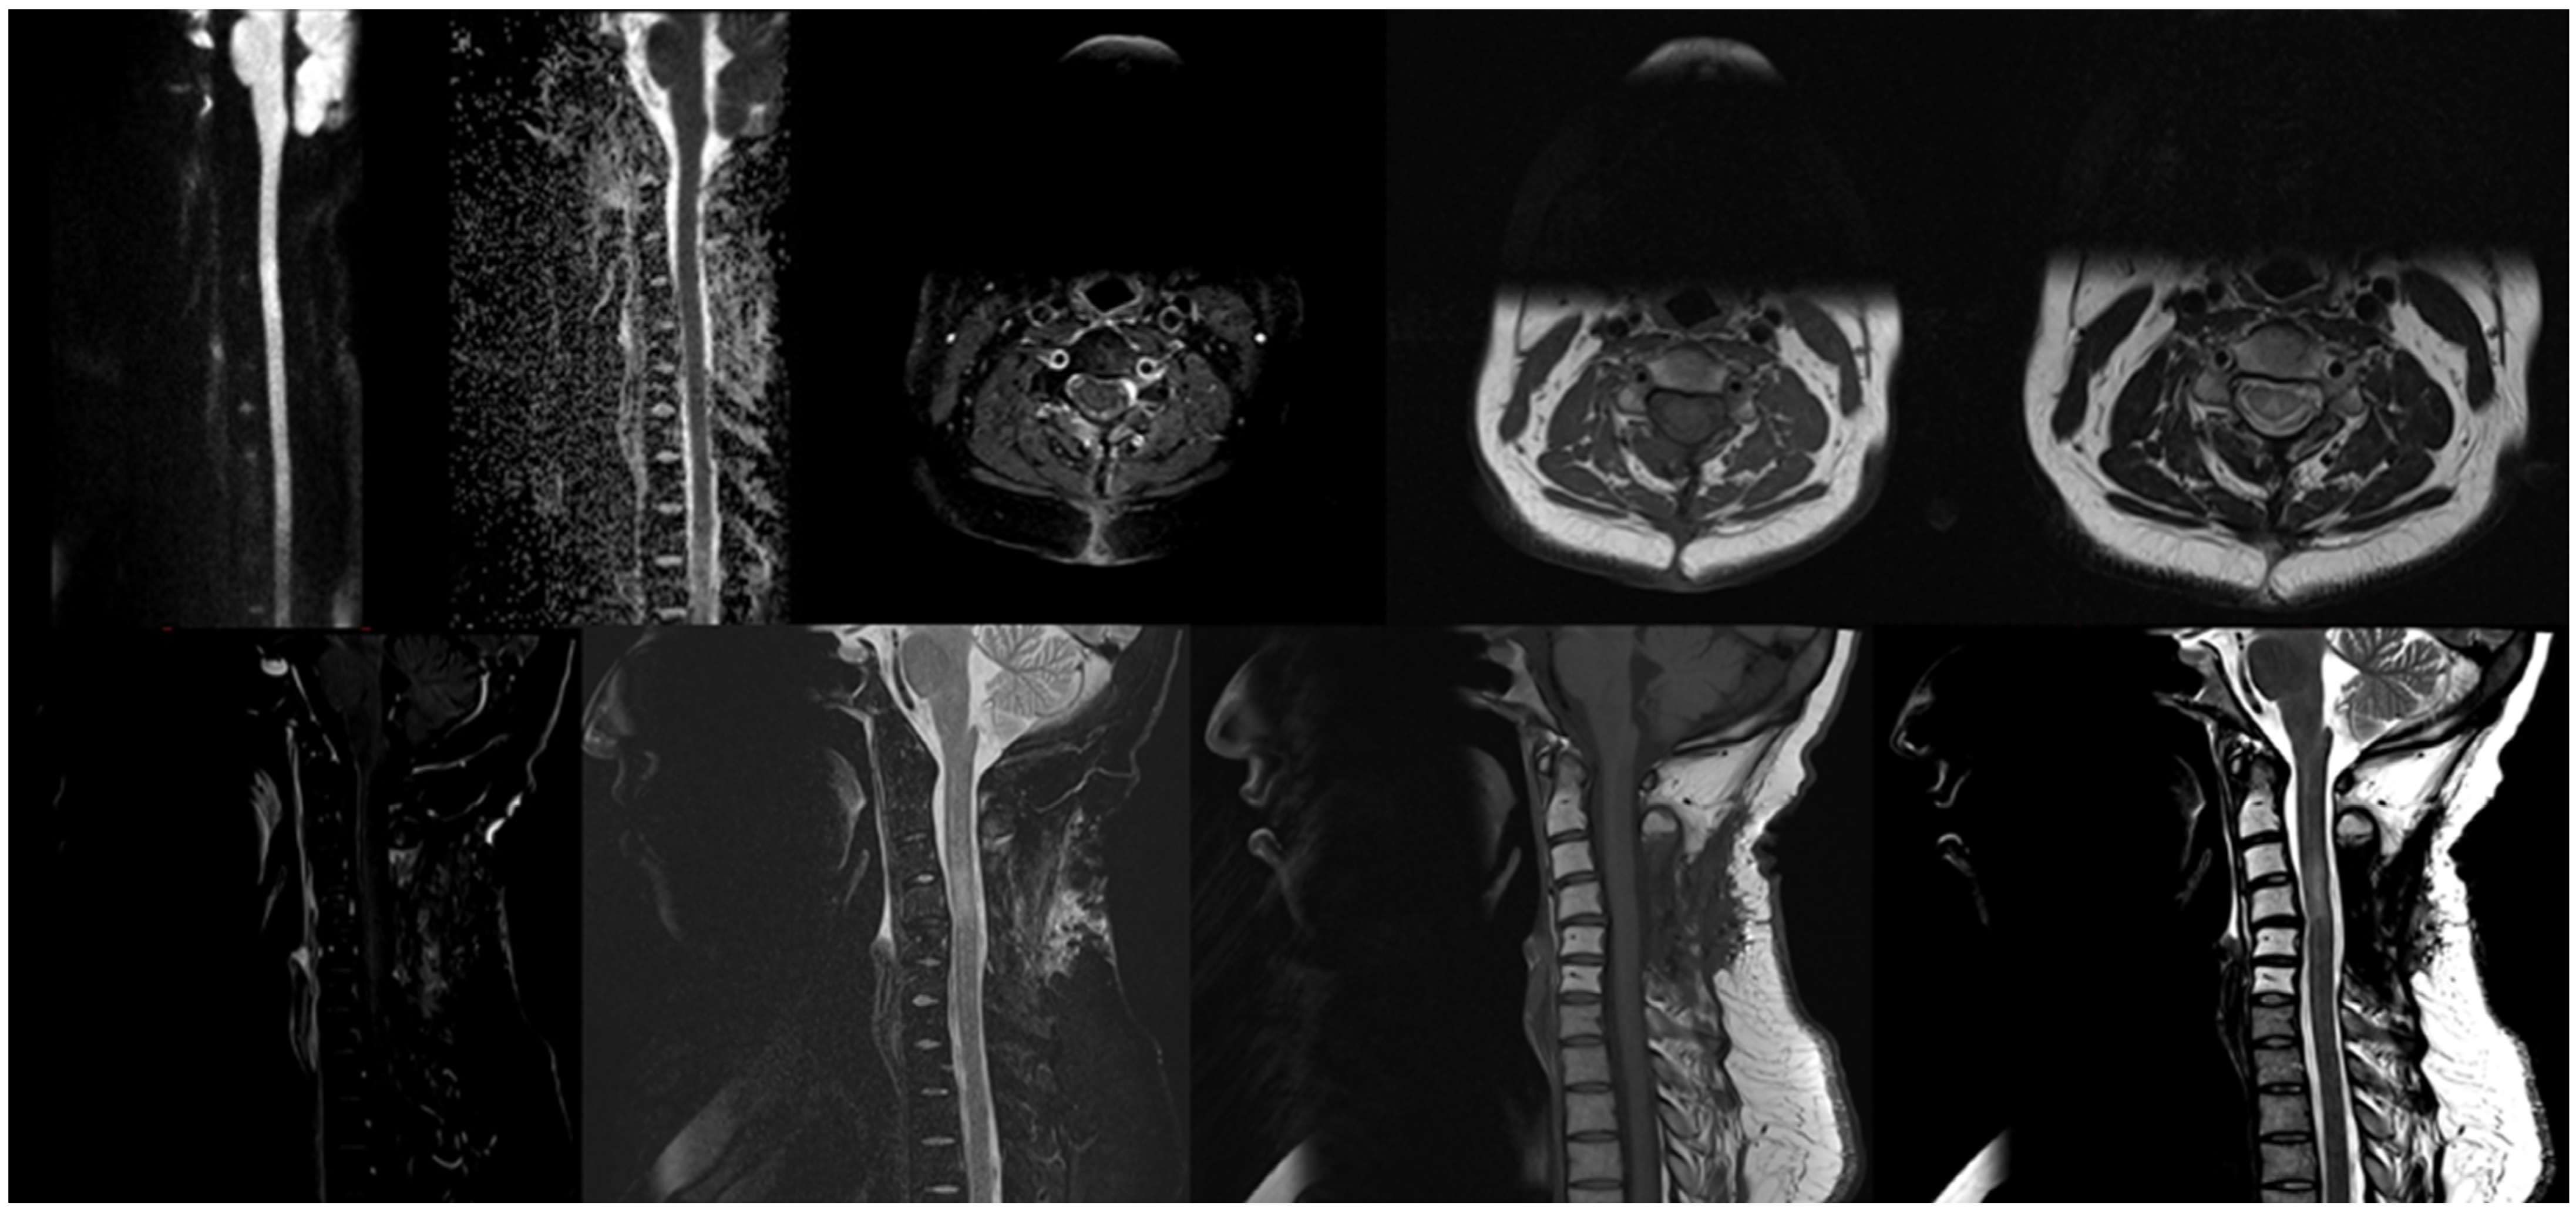

3. Case Description